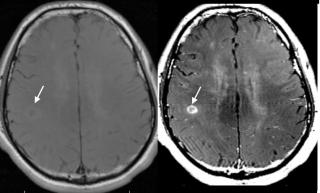

МРТ головного мозга с контрастом – это возможность исследовать и проверить, в каком состоянии находятся мозговые оболочки, белое и серое вещество мозга. С помощью контрастного усиления врачам удается обнаружить очень мелкие опухоли, метастазы, дифференцировать доброкачественную опухоль от кисты или рака, увидеть последствия перенесённых черепно-мозговых травм.